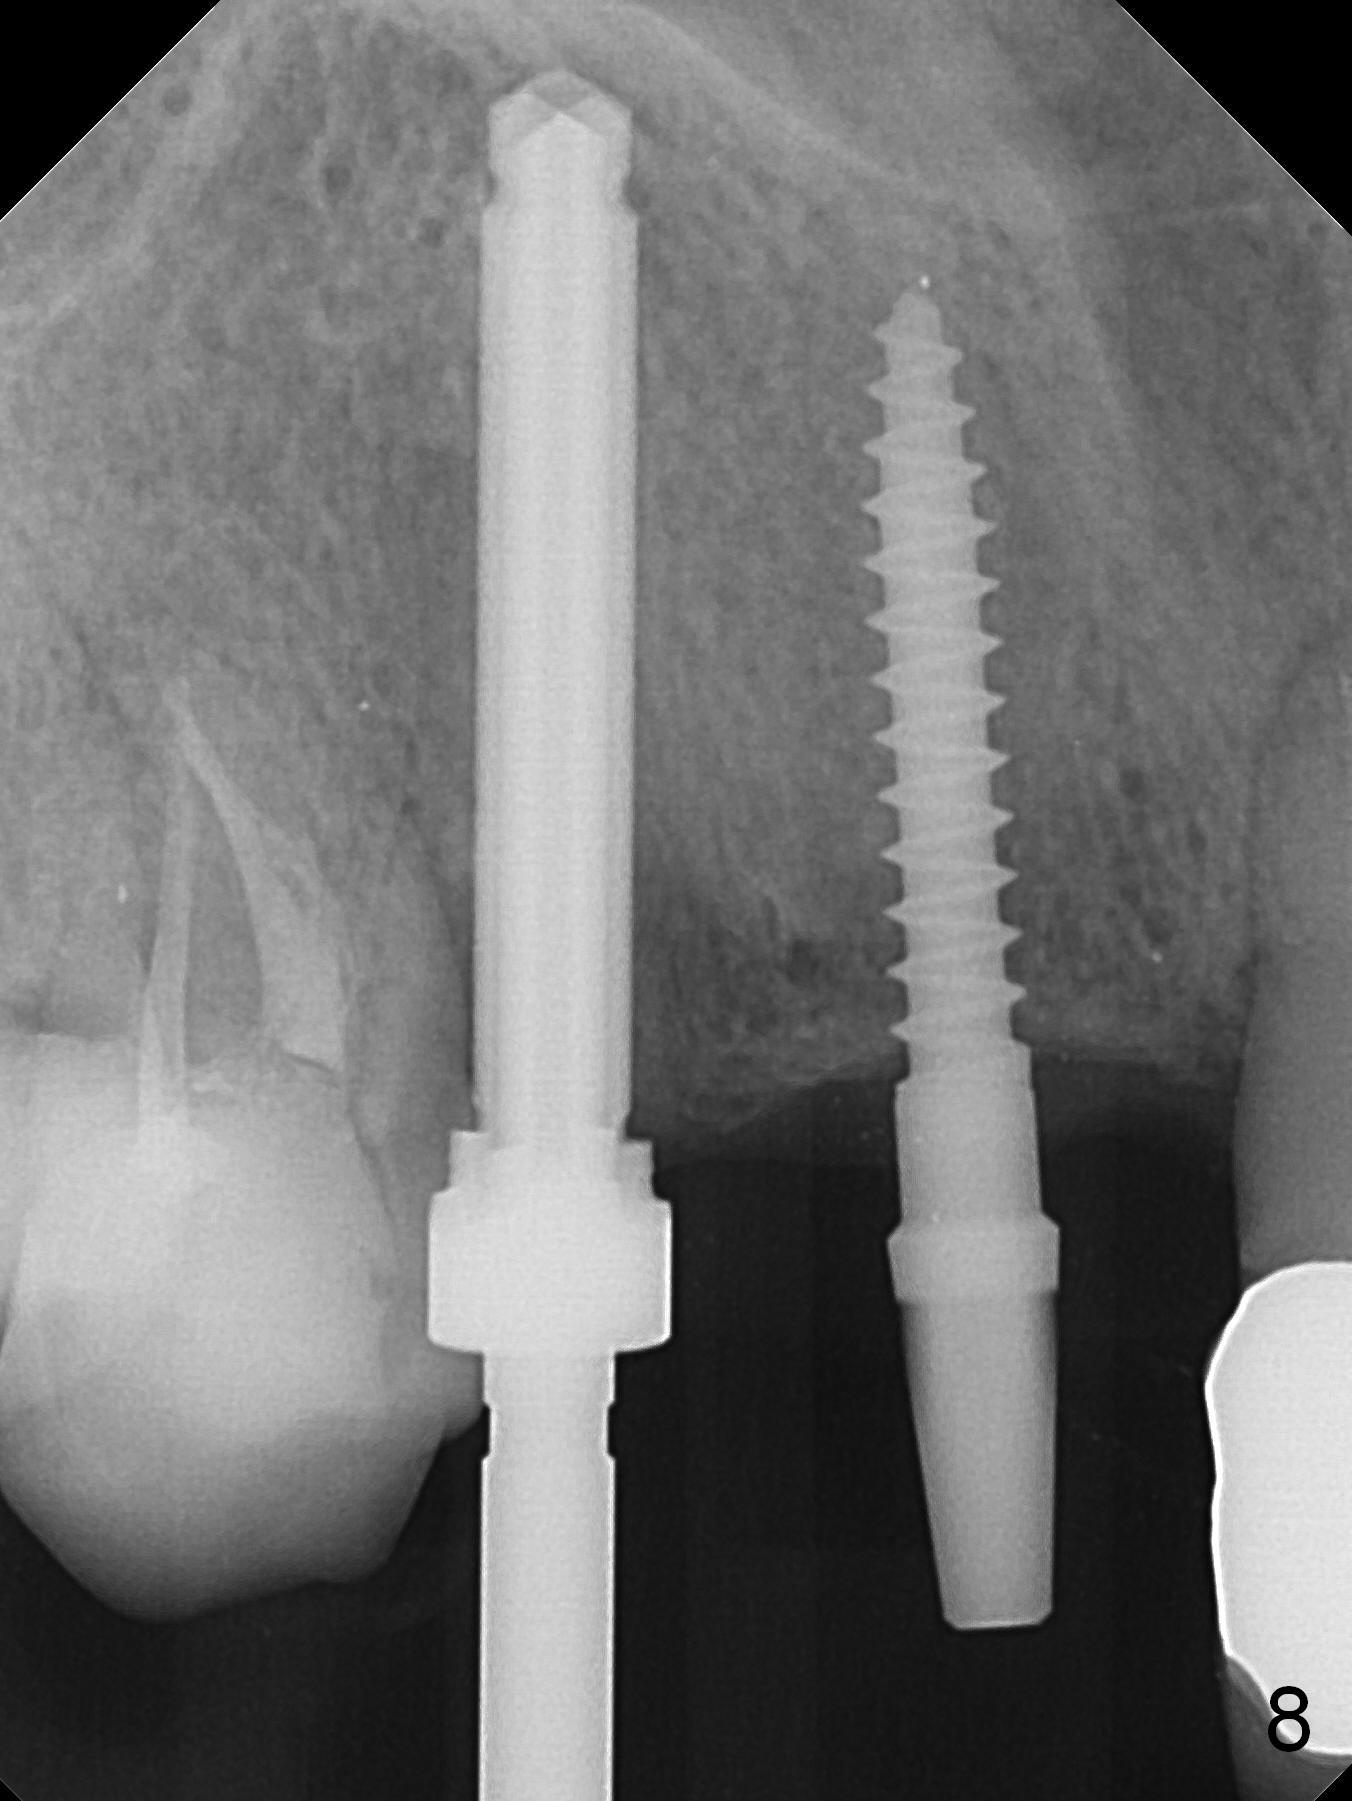

When the bridge is sectioned between #7 and 8, the tooth #6 is found non-salvageable (Fig.1).  Incision shows the atrophic buccal plate at #7 (Fig.2 arrowheads); to prevent the same feature from happening at #6 with thin buccal plate, the most buccal portion of the root is preserved (socket shield (Fig.2-4: *)).  The initial osteotomy is established in the palatal slope at #6 (Fig.5 circle) with 1.5 mm drill (Fig.6,7).  A portion of the root is visible in Fig.6 (arrowheads).  After sequential osteotomy with 2 mm, 3 mm (Fig.8) and 3.2 mm drills, a 4x15 mm implant is placed (Fig.10).  To accommodate the cross bite, the coronal portion of the implant (Fig.9 white circle) is positioned close to the socket shield.  It appears that the shield prevents the implant from encroaching the buccal plate.